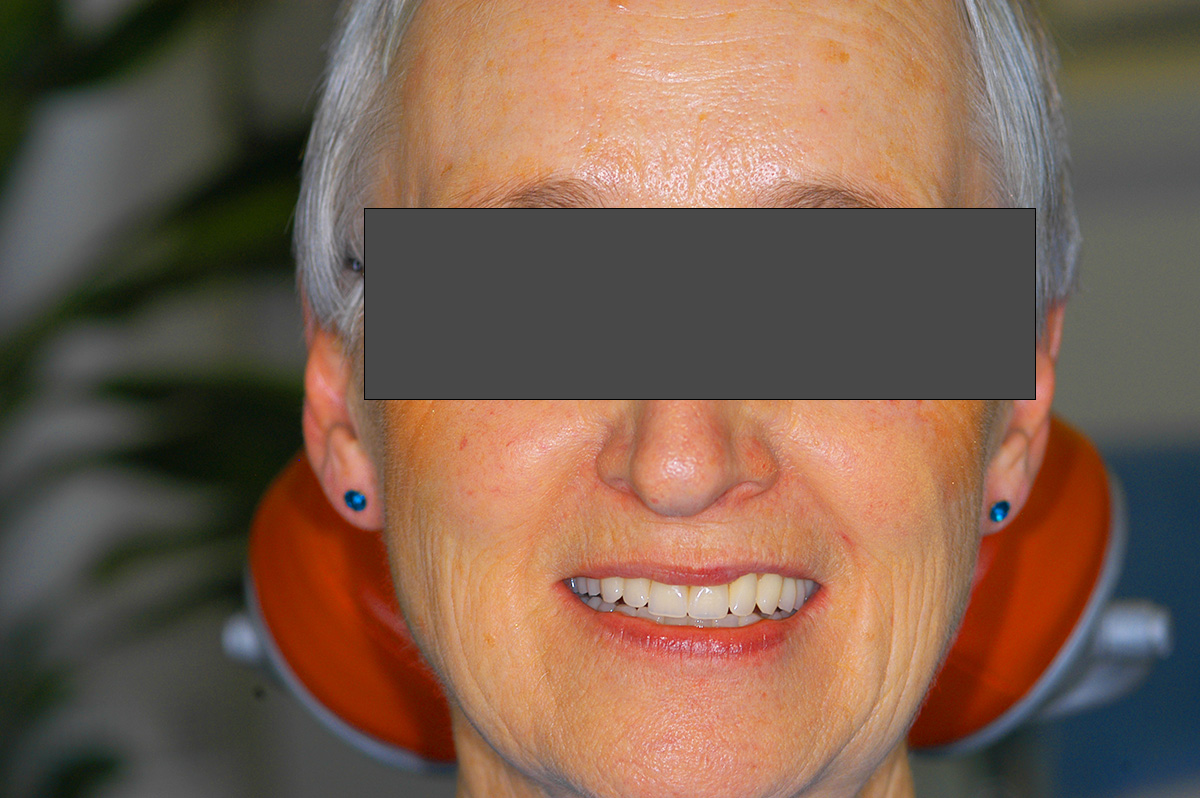

Vorher / Nachher

Beispiel 1